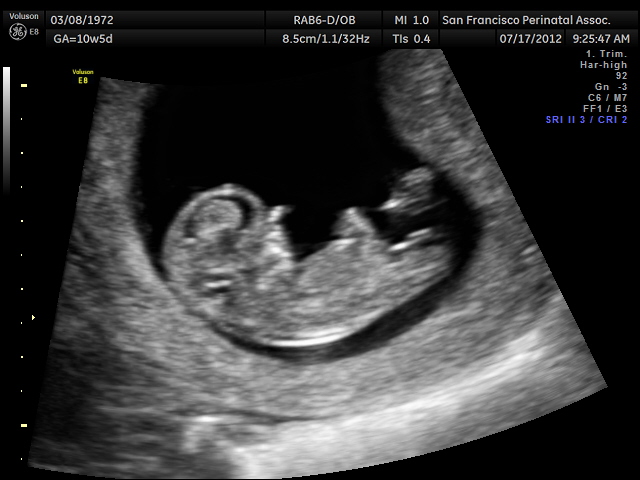

Rose's Ultrasound: 11 weeks, 2 days

This photo from my CVS ultrasound today. Although by last period, I am 10w5d, by size of baby, I am 11w2d. I know this is early, but I have seen all three of my boys by 12 weeks without any doubt, and to me, this looks like three lines. I have two other photos with a straight fork as well. Is it possible?

We will have the results in less than two days (rapid FISH results, just like 5 probe PGD... will tell us 13, 18, 21 and gender). But would love your feedback as well.